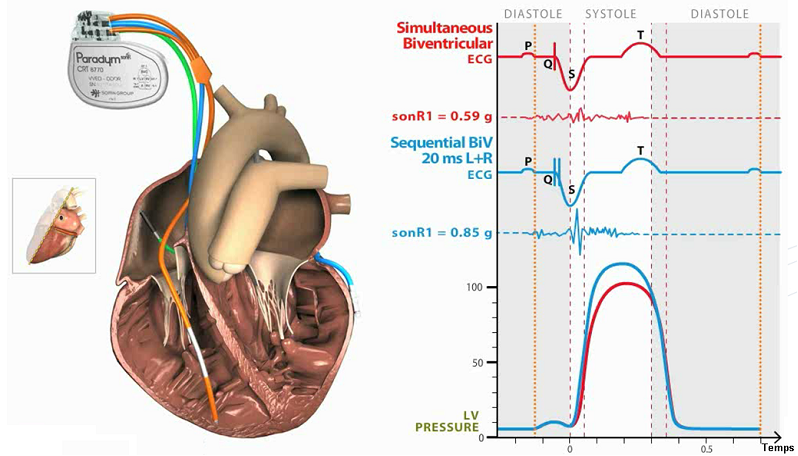

Le SonR® Le capteur hémodynamique micro-accéléromètre est enfermé dans une capsule scellée à l'extrémité d'une sonde de stimulation auriculaire (sonde SonRtip compatible IS-1).

Le capteur mesure en g (m/s2) les micro-accélérations du myocarde tout au long du cycle cardiaque ; le SonR1, l'un de ses principaux composants, est créé par la contraction iso-volumique.

La composante SonR1 de ce signal correspond au premier bruit cardiaque S1. Ses variations sont corrélées aux variations du VG maxdP/dt.

Les systèmes CRT-D SonR numérisent et analysent le signal SonR1 provenant de la sonde auriculaire. L'algorithme contenu dans ces défibrillateurs optimise automatiquement les délais AV et VV sur une base hebdomadaire.